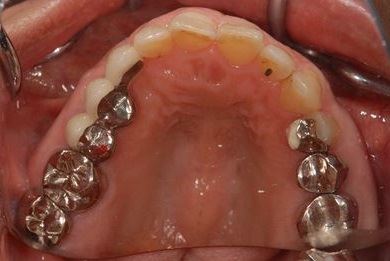

主訴 噛むと痛い。(咬合痛がある)

治療前

• 治療前